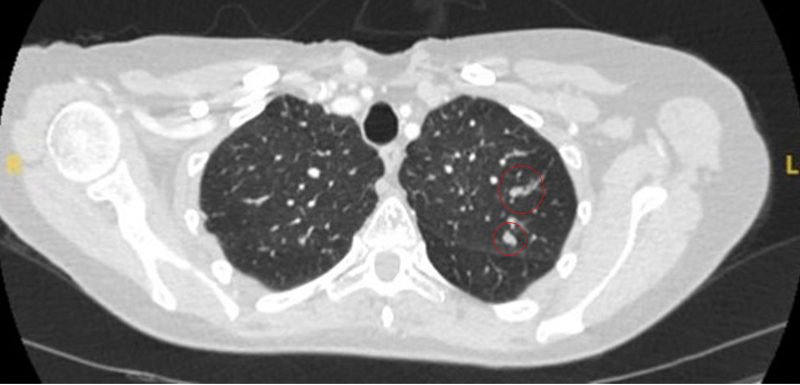

The remaining causes are infrequent and include mucoid impaction, septic emboli, arteriovenous malformations, and pulmonary amyloidosis.

[Figure caption and citation for the preceding image starts]: Computed tomography (CT) showing a left upper lobe peripheral elongated nodule, with contrast enhancement and a clear feeding and draining side, consistent with a small arteriovenous malformationFrom the collection of Dr George Tsaknis, MD, PhD, FRCP(London), MRQA, MAcadMEd, PGCert; used with permission [Citation ends].

[Figure caption and citation for the preceding image starts]: Computed tomography (CT) showing a right lower lobe large nodule, with contrast enhancement and a clear feeding and draining side, consistent with an arteriovenous malformationFrom the collection of Dr George Tsaknis, MD, PhD, FRCP(London), MRQA, MAcadMEd, PGCert; used with permission [Citation ends].